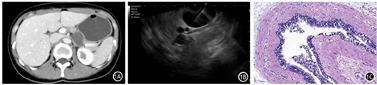

患者女性,32岁。因"体检发现胰尾占位性病变近2个月"入院。患者自觉无不适感,无特殊病史及不良嗜好,否认家族性遗传病,入院前肝胆胰超声示胰尾囊性占位,考虑胰腺囊肿可能。入院后体检未见异常,血清肿瘤标志物均在正常范围内。腹部CT增强扫描示肝胃间隙囊性占位,考虑良性病变(图1A);胆囊炎,胆囊周围炎;左肺下叶粗大血管伴局限性气肿可能。排除禁忌证后行Linear 7.5 MHz EUS检查,见胰尾部一无回声病灶,边界清楚,病灶管壁较厚,内有分隔,病灶内未见血管(图1B),考虑黏液性囊腺瘤可能。即刻在EUS引导下行细针穿刺抽吸囊液。生物化学检测示囊液淀粉酶44 900 U/L,CEA>1 000 U/ml,CA125 3013.00 U/ml,CA19-9正常;囊液涂片细胞学检查见囊液及少许上皮细胞,未见恶性肿瘤细胞。经与患者充分沟通并同意后转肝胆外科手术治疗。手术切除2 cm×2 cm×1 cm囊肿一枚,壁厚3 mm。手术标本病理检查见囊壁为纤毛柱状上皮,周围可见丰富的平滑肌组织,伴黏液样变性,局部间质有少量炎性细胞(图1C),诊断为胰腺纤毛前肠囊肿。术后患者恢复良好,出院后复查至今未见肿瘤复发或转移。